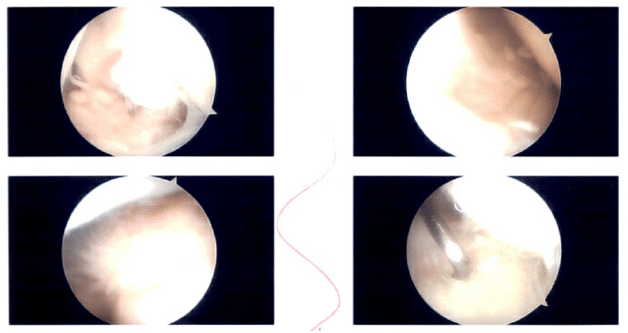

The scope was entered into the glenohumeral joint. An examination of the glenohumeral joint was performed. There was grade 3 to grade 4 arthritis of the glenoid as well as the head of the humerus. There was fraying of the labrum. The rotator cuff tear could be identified.

Intraoperative Shoulder Arthroscopic Images.

Debridement of the subscapularis, labrum was performed. Debridement of the head of the humerus was also performed. Marking PDS suture was passed through the rotator cuff tear. Now the scope was entered into the subacromial space. There was extensive bursitis. Subacromial decompression was performed using a shaver.